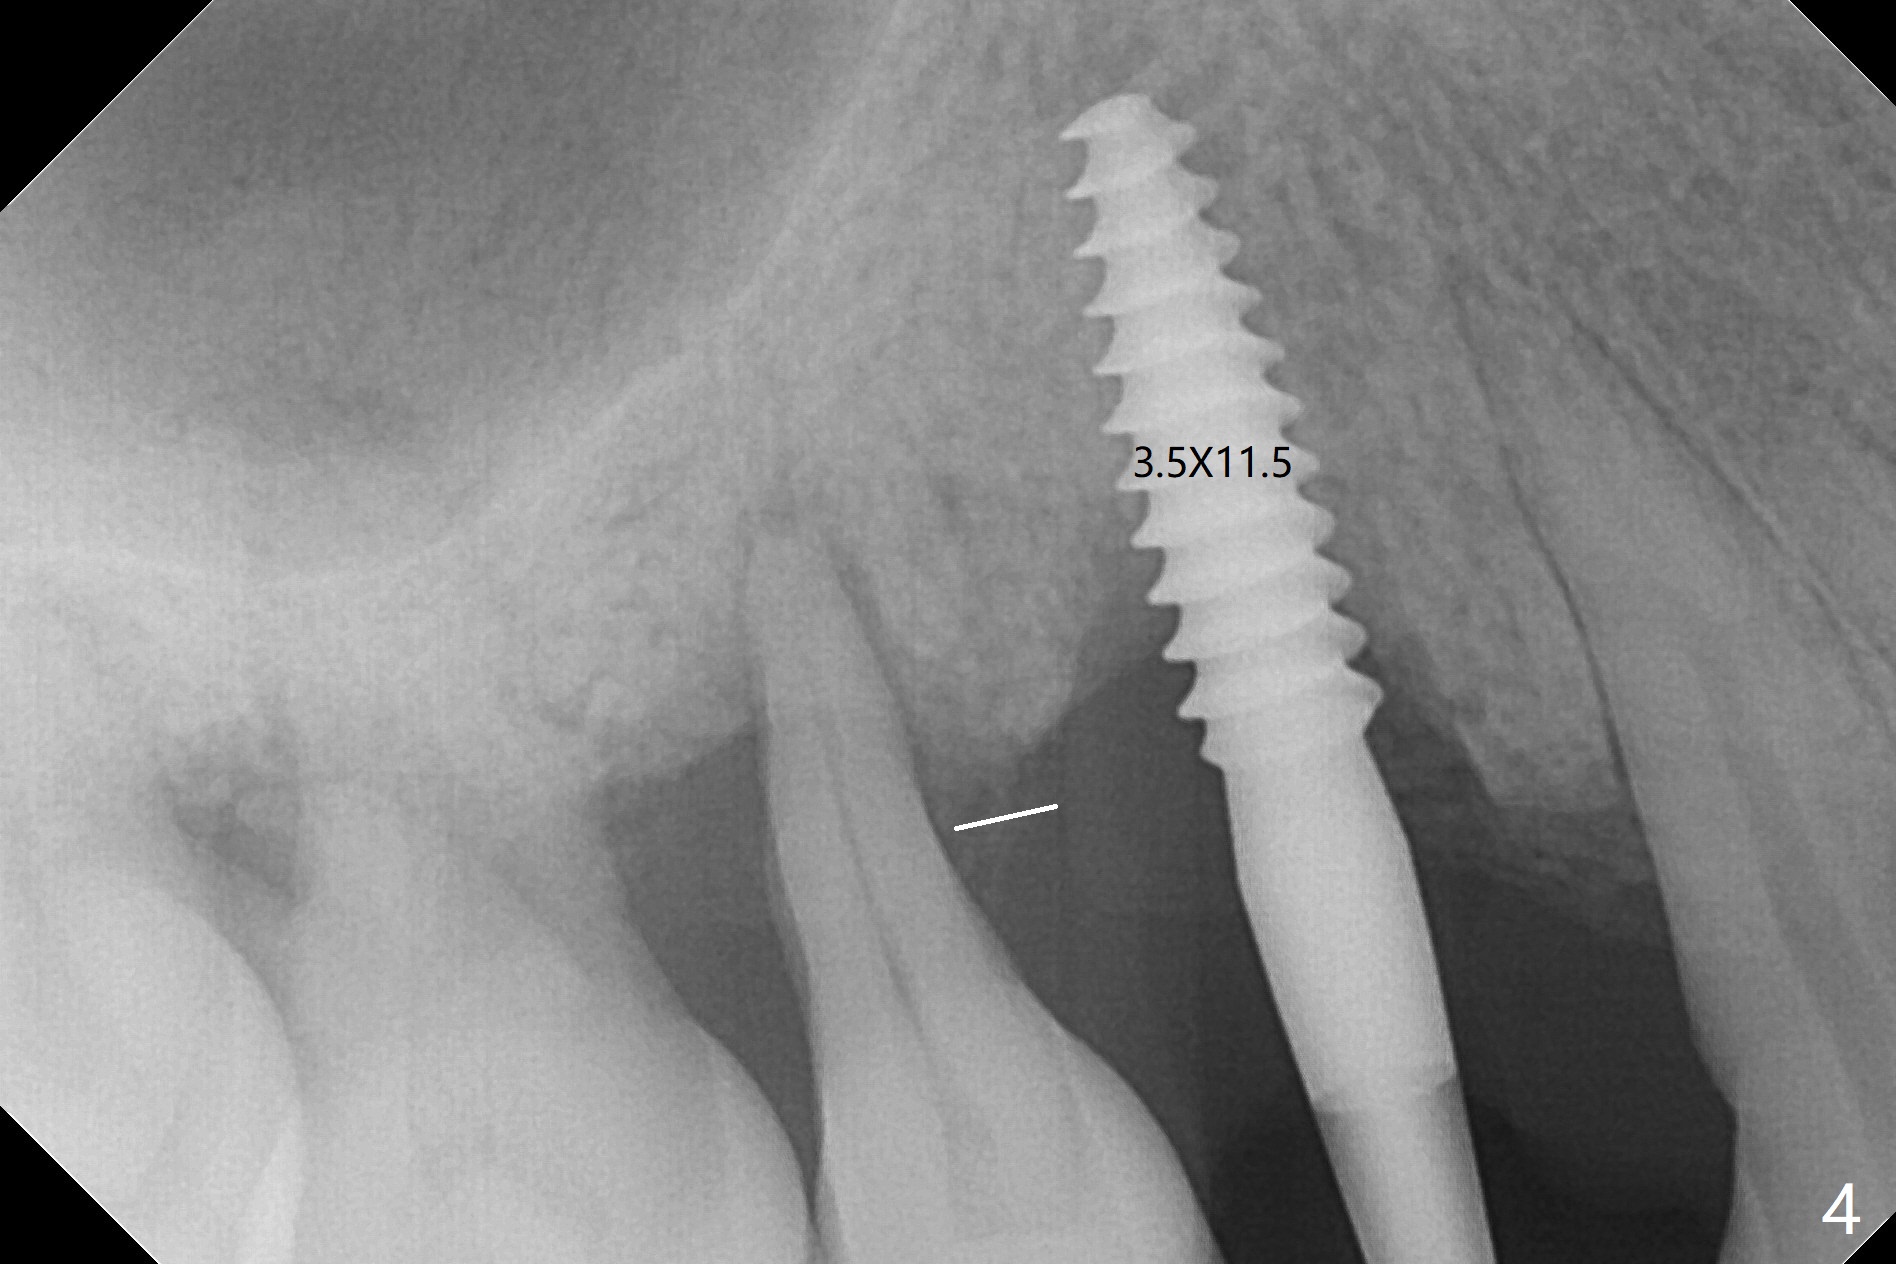

术前CT显示右上4牙槽骨比5窄(图一,二),3.5毫米植体比较合适,况且牙龈厚,基台长的一段式植体显得得当。为了取得最好的植体方位,4先拔除(图三),种植(图四),调整后者深度后,拔除5(术前征求病人同意),开始钻洞(图五),完成种植(图六)。粘性骨粉不仅放置于植体周围,而且6牙根近中(图七),4/5牙槽嵴和龈乳头(P)之间,减少术后龈乳头萎缩(图八:*)。制作两个分开临时牙冠,有利于维持龈乳头。对于病人来说,临时牙冠帮助咀嚼,而对侧拔牙创无法吃饭。术后3个月两个分开临时牙冠(其中一个龈方移位(图九:箭头)保持龈乳头(*)和牙龈外形(图十:*)。临时牙冠取出后,调整基台高度,少量钛屑(不妨大局)附着在健康的牙龈沟(图十一),再次显示两个基台之间龈乳头(图十二:*),衬里,修整的临时牙冠又插回牙龈沟(图十三:箭头),继续维持软组织形态,准备一个月后,调整基台边缘(图十二:箭头),取模。术后五个月大部分骨粉依然保留在植体和邻牙周围,龈乳头退缩不多(图十四: P)。三个月后(术后六个月)钛削无影无踪(图十五,与图十一对比))。永久性牙冠周围空间慢慢会消失(图十六,使用临时性胶水)。